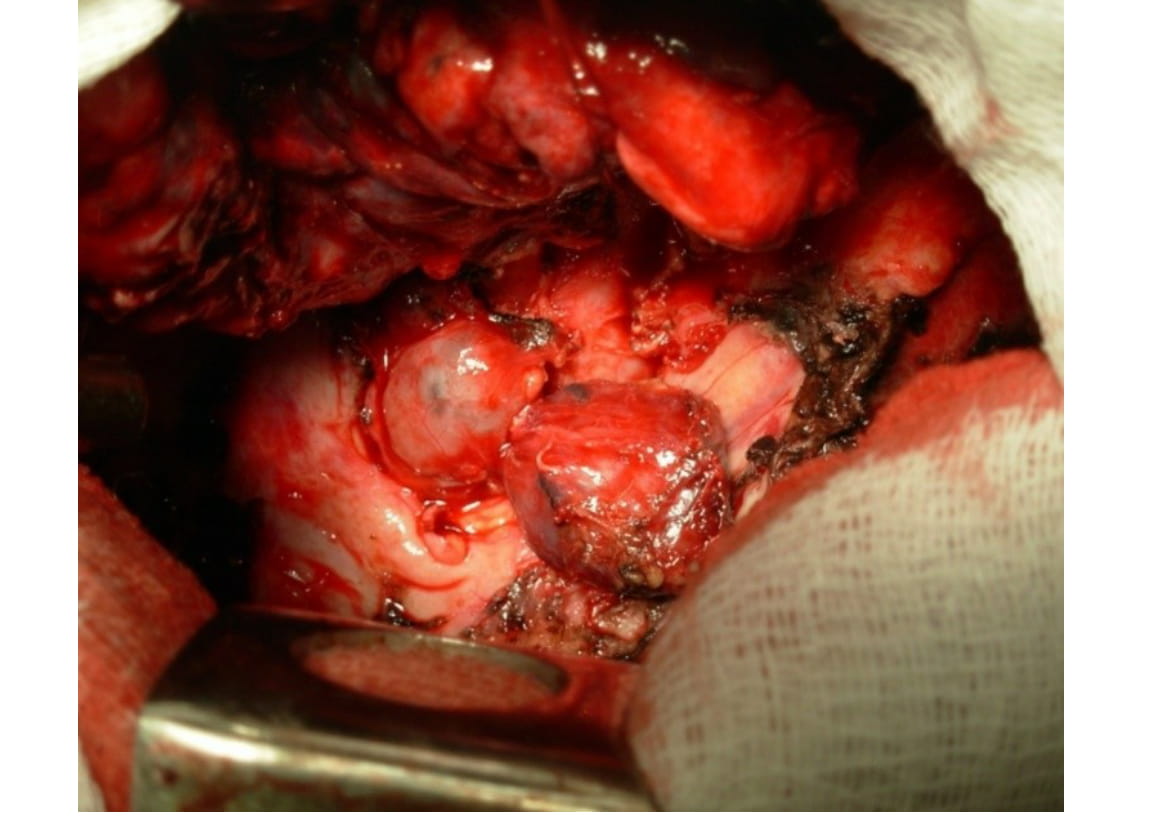

Patient G., 32 years of age, suffering from fibro-cavernous tuberculosis of the right lung in the phase of progression (Fig. 1) has been treated for 6 months conservatively with no effect, multiple drug resistance of Mycobacterium tuberculosis was detected. Pneumonectomy was performed, which revealed enlarged indurated and adherent to the surrounding tissues paratracheal, subcarinal and periesophageal lymph nodes (Fig. 2). Mediastinal lymphadenectomy was performed. On the cross-section of lymph node massive caseation was found (Fig. 3). Morphological analysis showed the presence of dry amorphous detritus with lymphoid elements and of single epithelioid cells in the peripheral areas (Fig. 4).

Fig. 2. Enlarged, indurated and adherent to the surrounding tissues mediastinal lymph nodes